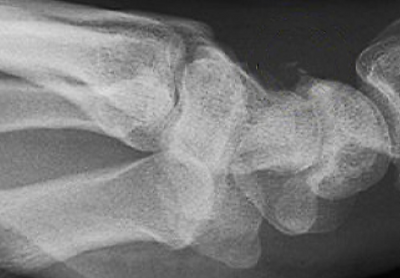

수골 X-Ray

근골격 MRI에서 손상 정도와 손상의 정확한 위치 파악

뉴로클의 소프트웨어는 주요 인대 혹은 힘줄 파열, 무릎 관절 내 중요한 구조물 손상 등을 특히 검출해내는 데에 용이합니다.

또한 각종 관절이나 뼈, 연부 조직의 외상이나 스포츠 손상부터 퇴행성 질환, 신경병증, 염증성 질환, 감염, 종양을 탐지할 수 있습니다.